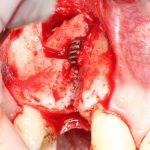

Осталось только наложить швы:

и подождать 3-4 месяца до интеграции имплантов.